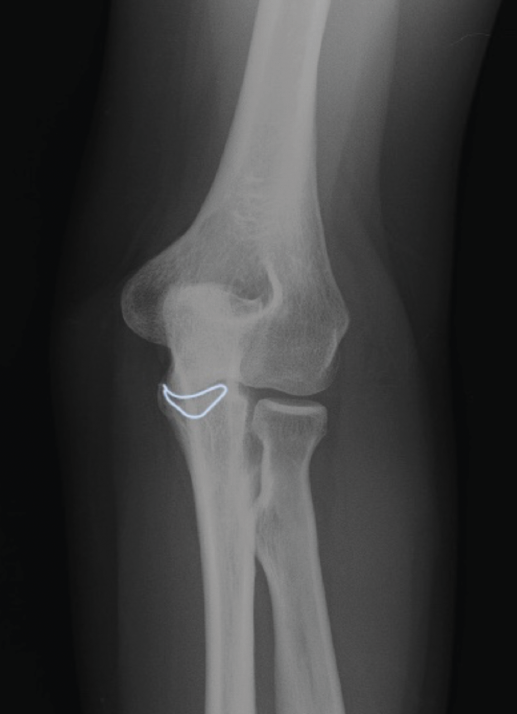

Presentamos el caso de una mujer de 46 años, diestra, sin patología crónica y que trabaja como auxiliar en una residencia geriátrica. Durante su jornada laboral sufre una caída casual presentando dolor y limitación funcional en su codo izquierdo. No presenta deformidades externas en el codo, ni lesiones vasculonerviosas. En el estudio radiológico, se sospecha una fractura de la punta de la apófisis coronoides del codo izquierdo, que correspondería, según la clasificación de Regan y Morrey, al tipo 1 (Figuras 1 y 2). Se comprueba que el codo es estable y se coloca una férula braquial, a la espera de realizar una tomografía computarizada (TC), que confirma la lesión. En la TC podemos visualizar mejor la morfología de la fractura de coronoides tanto en los cortes sagitales (Figura 3), como en los axiales (Figura 4).

Figura 2. Radiografía anteroposterior del codo izquierdo. Se enmarca la línea de fractura de la apófisis coronoides que se extiende hacia ambos lados hacia la base de la misma.